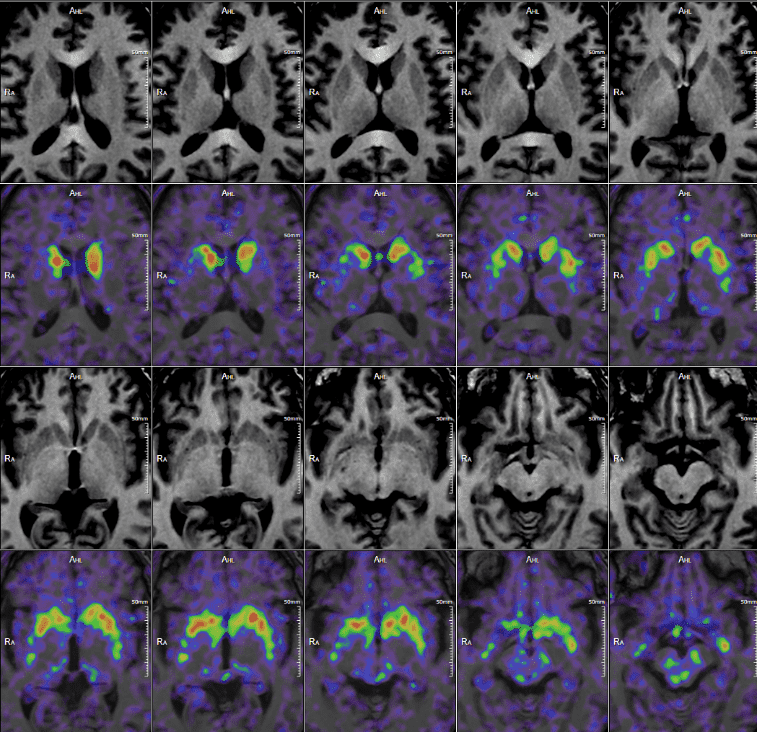

PET/MRI of the Brain with Parkinson’s

18F-DOPA used for diagnosing Parkinson's disease populations